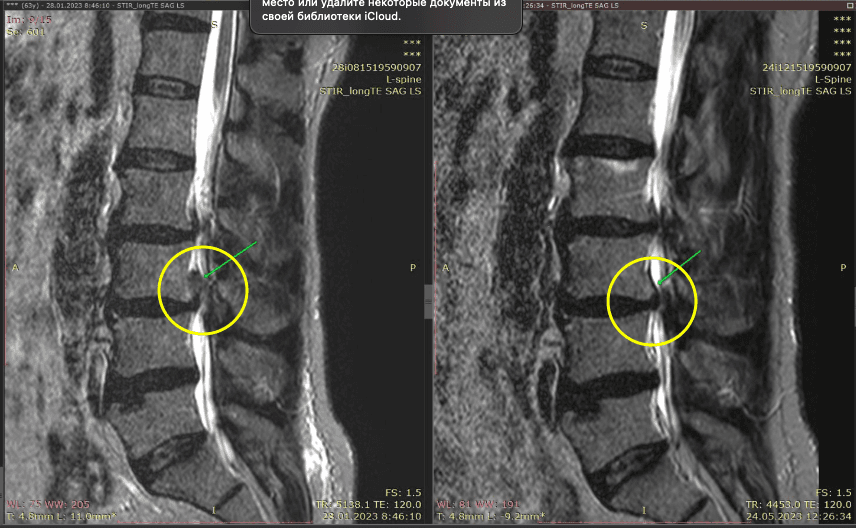

Метод лікування грижі шляхом стимуляції резорбції в Україні був впроваджений у 2020-2021 роках.  Алгоритм оцінки грижі на предмет резорбції, що використовується у клініках – є авторським, розроблений лікарем Боханом А.Ю.